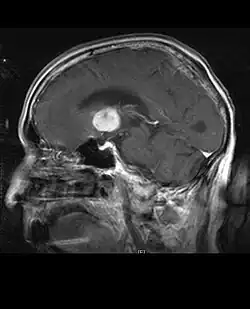

Astrocitoma anaplásico

Astrocitoma anaplásico é um tumor cerebral maligno caracterizado por crescimento difuso, aumento da densidade celular e figuras de divisão nuclear. Ele surge de uma população de células específicas do sistema nervoso central, os astrócitos. De acordo com a classificação da WHO de tumores do sistema nervoso central, o tumor corresponde a um tumor de grau III. Normalmente, os pacientes com astrocitoma anaplásico apresentam crises epilépticas, déficits neurológicos focais, dores de cabeça e alterações de personalidade. A idade média dos pacientes é de 45 anos. A ressonância magnética geralmente mostra uma lesão maciça com sinal de contraste aumentado, que também pode ser mais fraco. O diagnóstico é feito pelo exame histológico da lesão por biópsia ou ressecção cirúrgica.

Um pior prognóstico pode estar associado à idade avançada, má condição física e danos neurológicos significativos. Em geral, o resultado terapêutico é melhor com ressecção cirúrgica completa (tratamento padrão) sem aumentar os déficits neurológicos. A radioterapia é padrão porque demonstrou aumentar o tempo de sobrevida. O papel da quimioterapia é controverso.